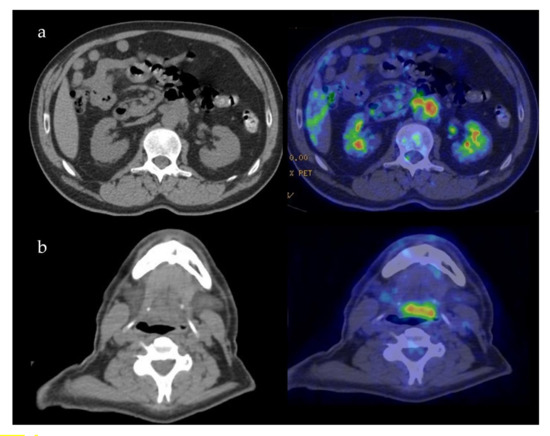

| 5 | 57, M | Tongue base extending to oropharynx | Retroperitoneum encasing aorta | 28 | 1.3 | 30 |

| 5 | Tongue: undiagnostic. Retroperitoneum: IgG4+: > 100 × HPF, IgG4+/IgG+ plasma cells > 40% | Prednisone 0.6 mg/kg/die and gradual tapering. Marked improvement. | |